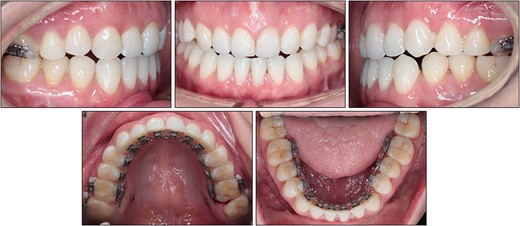

After treatment, class I canine and molar relationships were obtained on both sides with a normal overjet and positive overbite (Fig. 5). The posttreatment lateral cephalometric evaluation showed an improvement in both anteroposterior (point A-nasion-point B angle, 3.1°) and vertical dimensions (Frankfort mandibular angle, 31.0°). The posttreatment panoramic radiograph showed adequate root parallelism without any sign of root resorption (Fig. 6). The lateral cephalometric superimpositions confirmed the intrusion of the maxillary molars, the extrusions of the incisors, and the counter-clockwise autorotation of the mandible (Fig. 7).